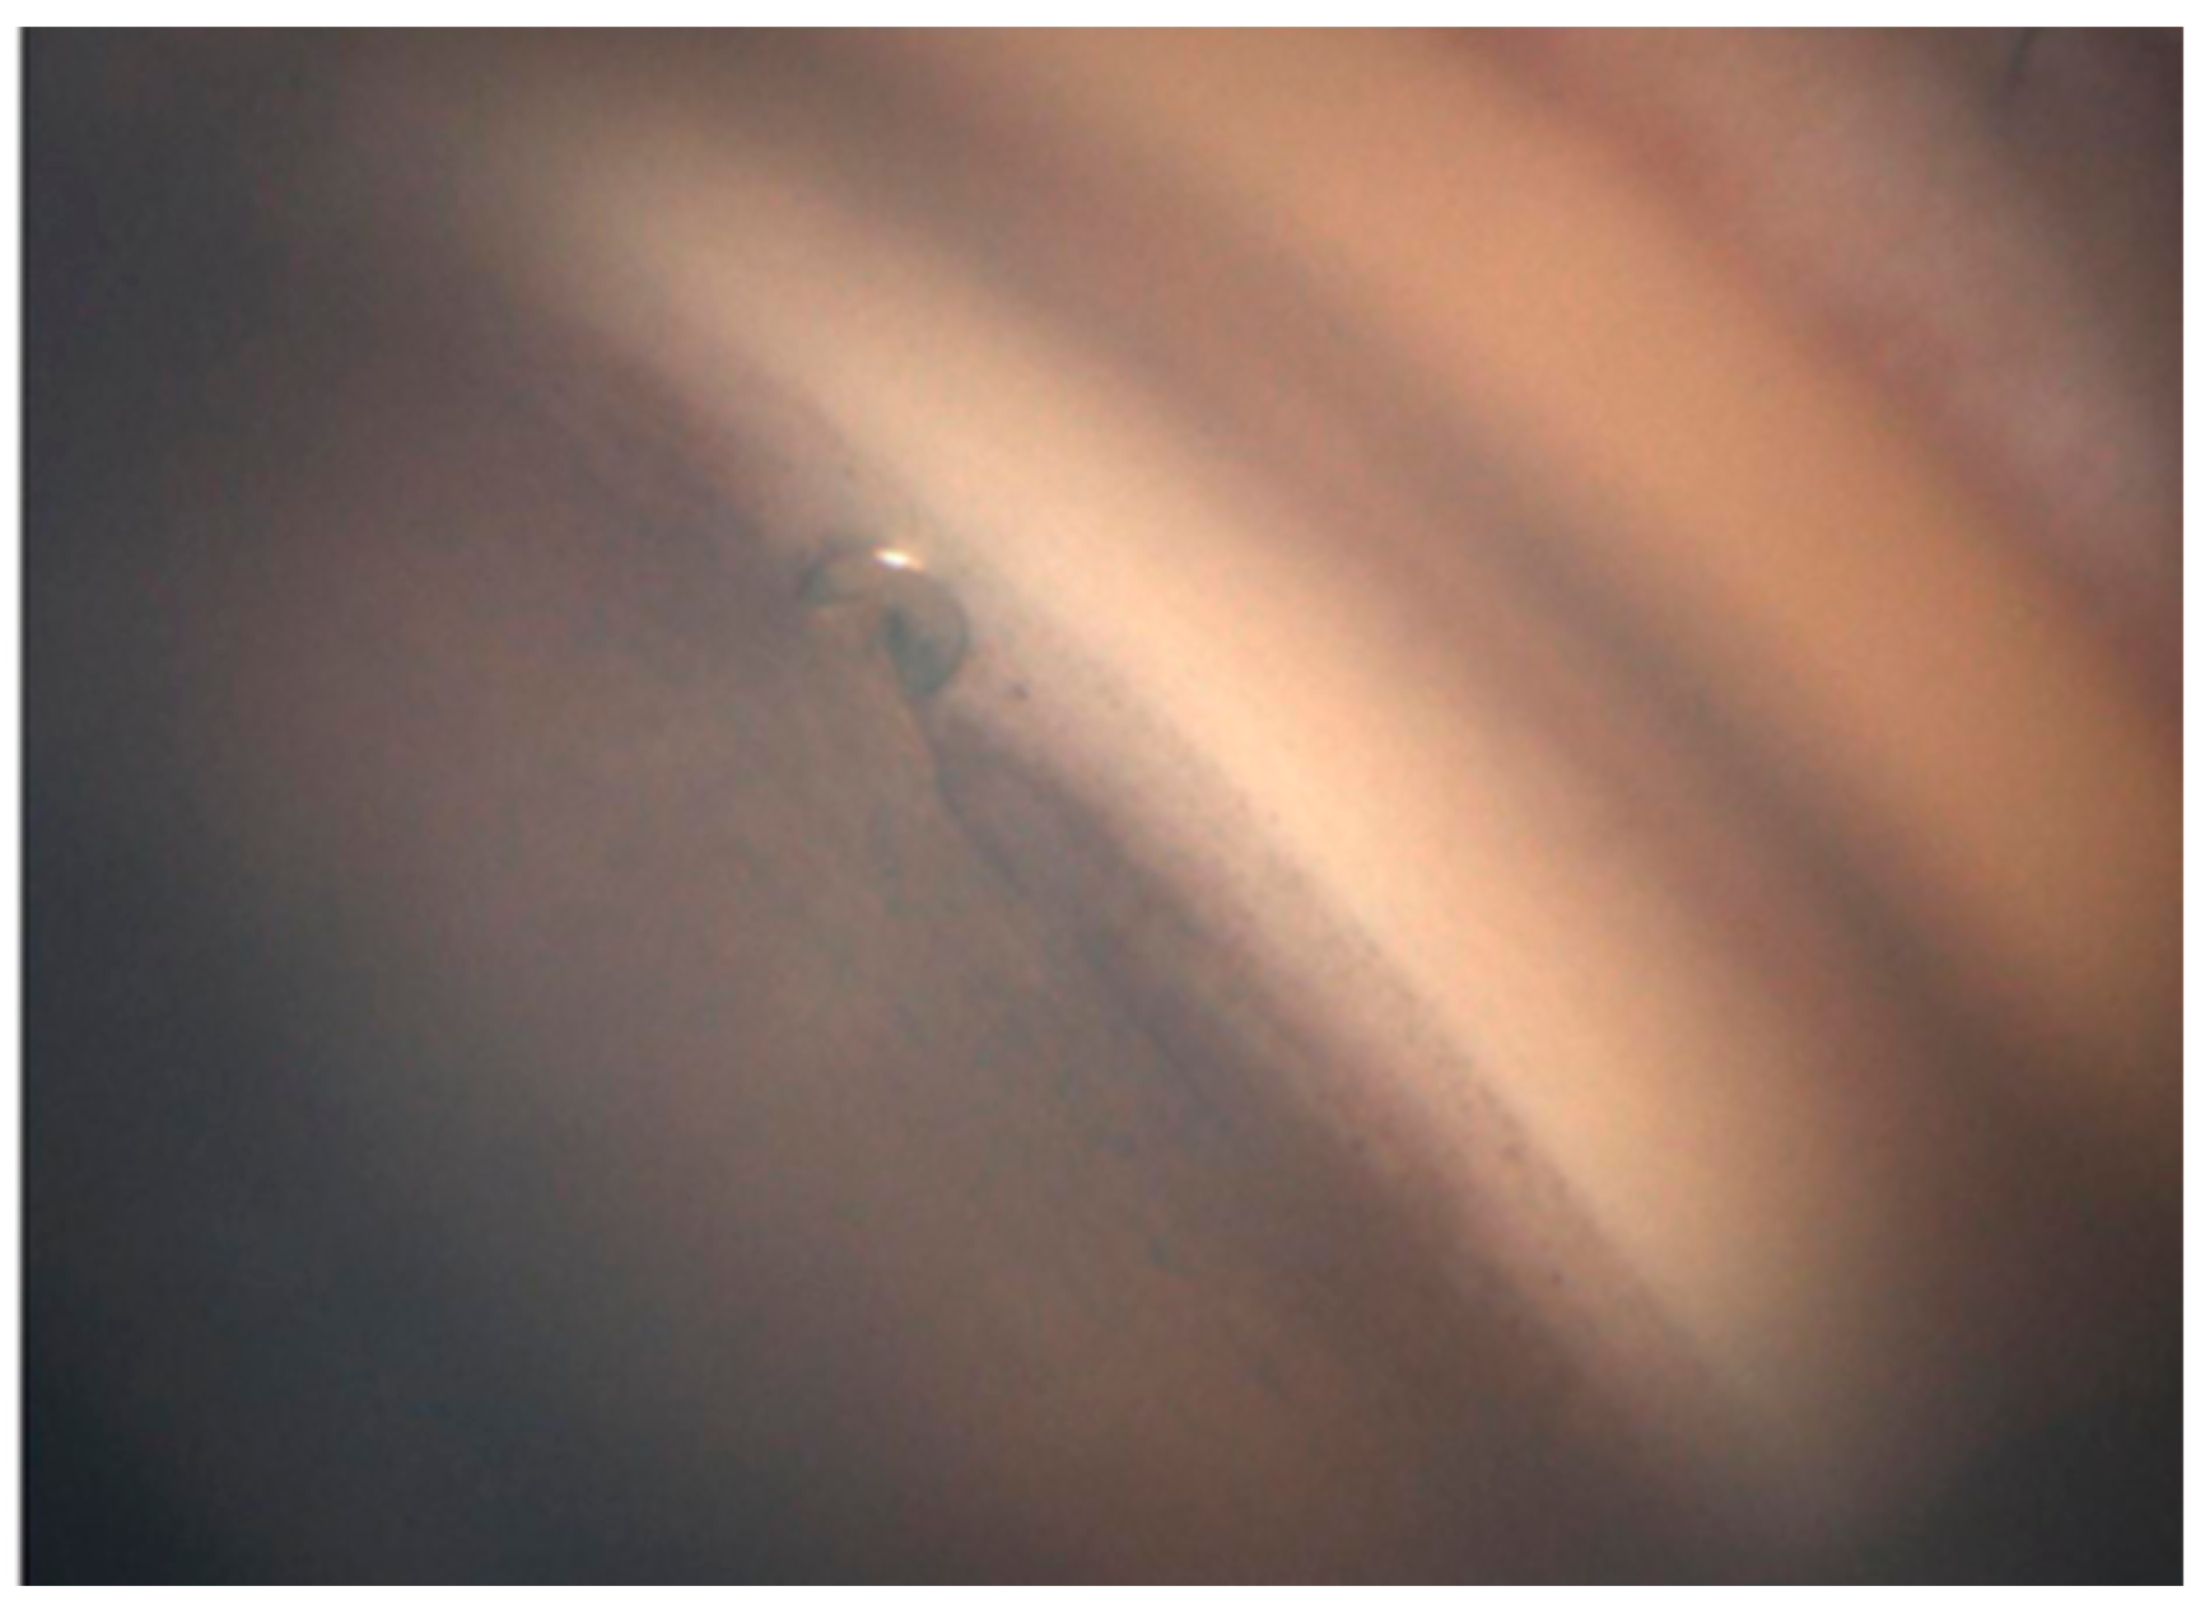

2.2. Automated Gonioscopy

Orthoptists obtained GS-1 images under bright illumination after topical anesthesia with oxybuprocaine hydrochloride. A single grader determined the implantation site and insertion depth based on the 16 directional images. The locations were graded according to the scheme of Zimmerman as follows: Grade 1, implant center over the nonpigmented to pigmented TM; Grade 2, within the pigmented TM; Grade 3, from the pigmented TM toward the scleral spur; and Grade 4, below the scleral spur within the ciliary body band. Insertion depth was graded based on the criteria described by Gillmann et al. [18,19], focusing on the relationship between the anterior chamber-facing superior edge of the flange and the TM. Grade 1 denoted the edge being external (anterior) to the TM, while Grade 2 denoted it being within the TM (Figure 1). We assessed whether the PAS abutted the flange based on the GS-1 images (Figure 2) and whether a TM cleft surrounded the implant (Figure 3). The same graders repeated the assessments on separate days to ensure reproducibility.

Figure 1. Grading of iStent inject W insertion depth. (A) Grade 1—superior edge of the flange protruding into the anterior chamber. (B) Grade 2—superior edge of the flange located within the trabecular meshwork.